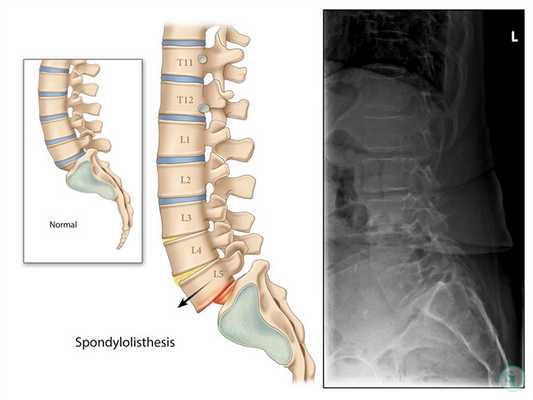

Спондилолистез шейного и пояснично-крестцового отделов

Термин спондилолистез означает соскальзывание позвонка. В результате этого происходит смещение одного из позвонков относительно нижележащего, что способно приводить к возникновению неврологических нарушений и ряда других осложнений. В большинстве случаев страдает шейный и поясничный отделы позвоночника, особенно часто обнаруживается спондилолистез L5-S1, L4-L5, C3-C4.

Основной причиной того, что возникает спондилолистез пояснично-крестцового отдела позвоночника или другой области, является разрушение или изначально недостаточное сращение соединяющей суставы дужки позвонка. Травмы, артроз, остеохондроз и другие подобные заболевания провоцируют усиление дефекта, в итоге позвонок становится подвижным и соскальзывает с поверхности межпозвоночного диска.

При выдвижении позвонка назад диагностируется задний спондилолистез, при смещении вперед - передний. Иногда встречается комбинированные деформации, при которых позвонки смещаются в разных направлениях. В отдельных случаях, особенно на фоне артроза или остеохондроза, наблюдается лестничный спондилолистез шейного отдела, для которого типично одновременное смещение нескольких позвонков в одном направлении.

Для выбора правильной тактики лечения важно дифференцировать ложный спондилолистез L4-L5 и других сегментов, так как для этого вида нарушения не характерно патологическое изменение межсуставной дужки. При псевдоспондилолистезе сегменты смещаются из-за присутствия анатомических особенностей позвоночника при резких движениях. Но диагностирование такой формы заболевания не означает, что она не способна привести к ущемлению нервов и другим нарушениям. Как и истинный спондилолистез L3-L4, она требует лечения, но оно будет носить несколько другой характер.